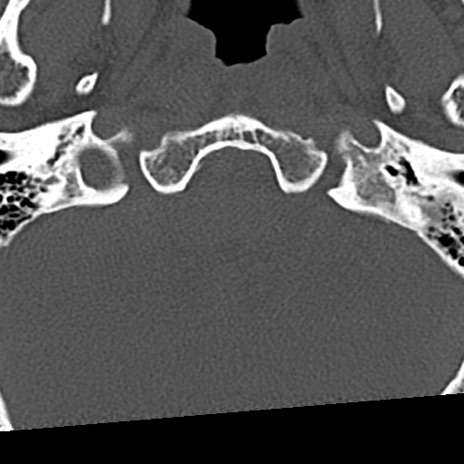

頚椎CT

冠状断像